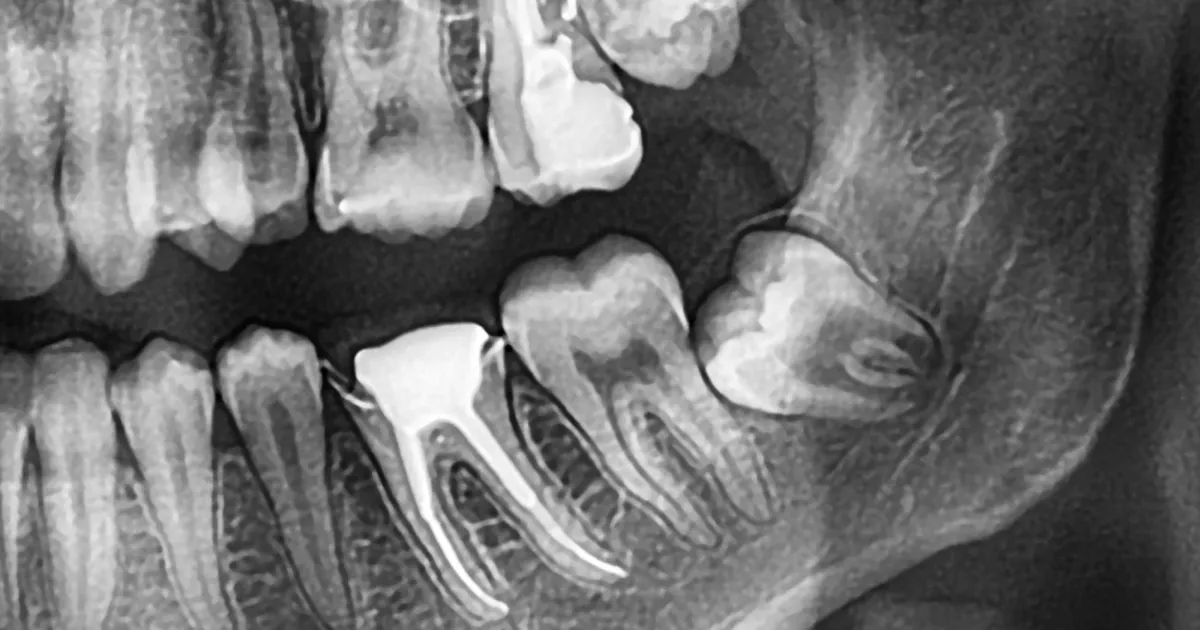

親知らずは「埋伏歯」や「水平埋伏歯」など、歯茎や顎骨内に埋まっていることが多く、周囲の組織を刺激してしまうことで腫れが生じることもあります。

また、骨を削ったり歯を分割して取り出す処置は外科的侵襲(刺激)が大きくなるため、術後の炎症が強く出ることがあります。